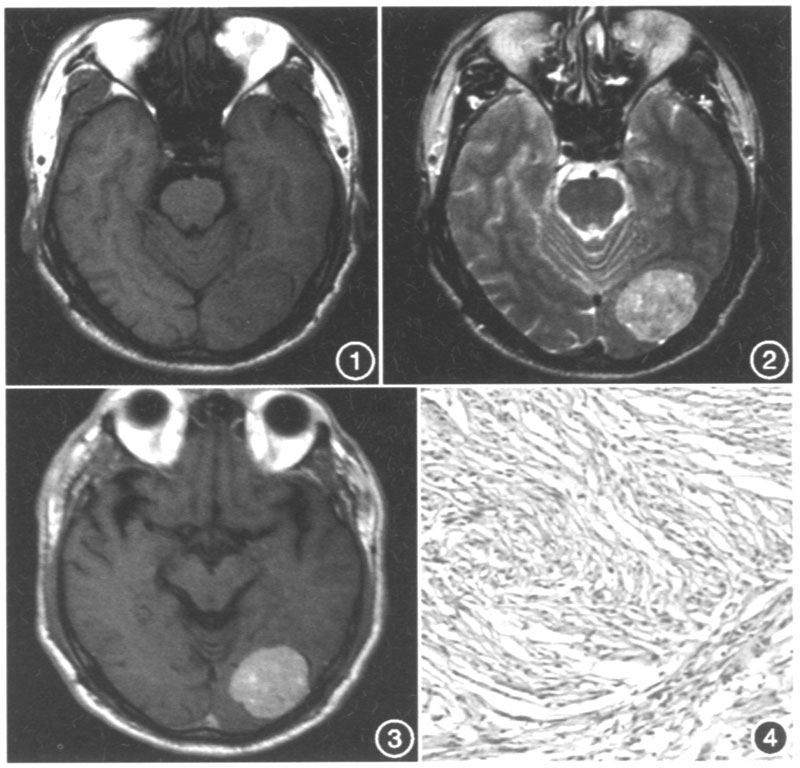

影像总结丨脑膜三件套——脑膜瘤,hpc/sft

special report: neuro-oncology

总之,"脑膜尾征"是影像学一个重要征象,经常出现在脑膜瘤中,但也不是